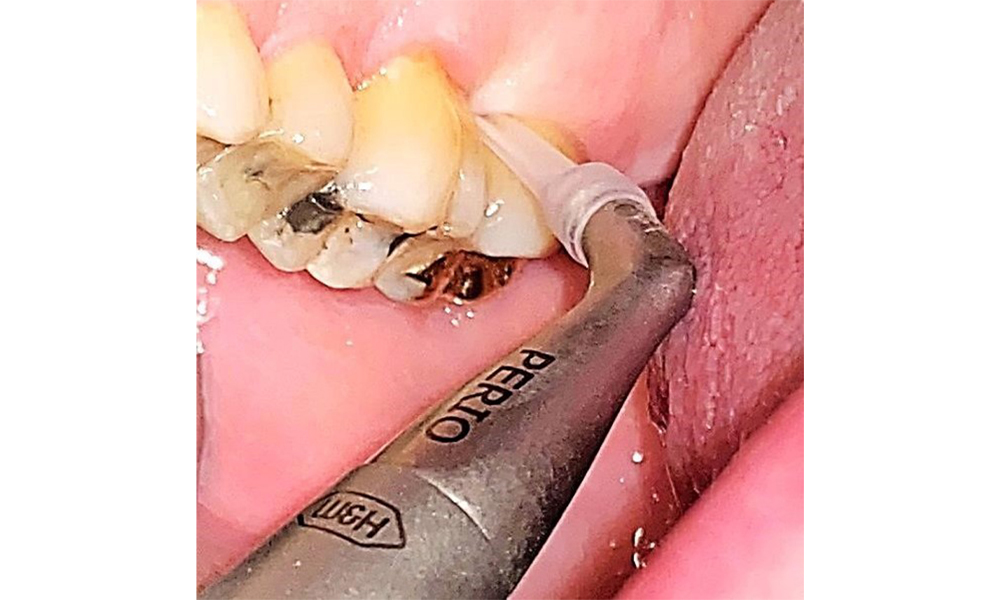

The documentation of periodontal findings, including pocket depth probing and bleeding status, is mandatory during each dental appointment due to the presence of periodontitis (Fig. 8). This will record the individual therapeutic needs and facilitate a rapid response to any progression of the pre-existing periodontitis.

There are no limitations regarding the choice of instrumentation methods. Regular supragingival and subgingival instrumentation is essential to prevent disease progression due to the pre-existing periodontitis and high risk of recurrence. There are no limitations placed on the selection of instruments for mechanical biofilm removal from a general medical perspective, and removal should be performed as needed. Hard and mineralized plaque, such as calculus and concretions, should be removed using manual instruments or sonic/ultrasonic scalers (Fig. 9) (8, 9).